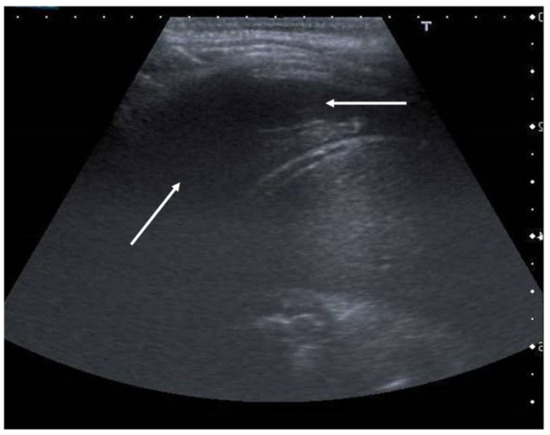

The role of LUS in identifying pleural effusion is also well established [53]. In fact, many studies have evaluated the efficacy of lung ultrasound in the diagnosis of pleural effusion, calculating its sensitivity and specificity, which have often been close to 100% [54]. These studies have confirmed the superiority of ultrasound over CXR in pleural effusion detection due to the capability of ultrasound to detect fluid collections as small as 20 mL [55]. Usually, pleural effusion can be visualized by ultrasound as a dark and anechogenic region located above the diaphragm that also determines the disappearance of the mirror image of the liver and spleen in the lung fields, which can be visualized in the healthy lung (Figure 10) [14]. Ultrasound also allows quantifying the amount of fluid accumulated in the pleural cavity well and characterizing the fluid collection differentiating a transudate from an exudate. The transudate is characterized by a dark image without internal echoes, representing an uncomplicated collection, while an image characterized by a septate or multiloculated corpuscular fluid collection is typical of the exudate [14].

Anechogenic fluid collection above the diaphragm suggestive of pleural effusion (white arrows).